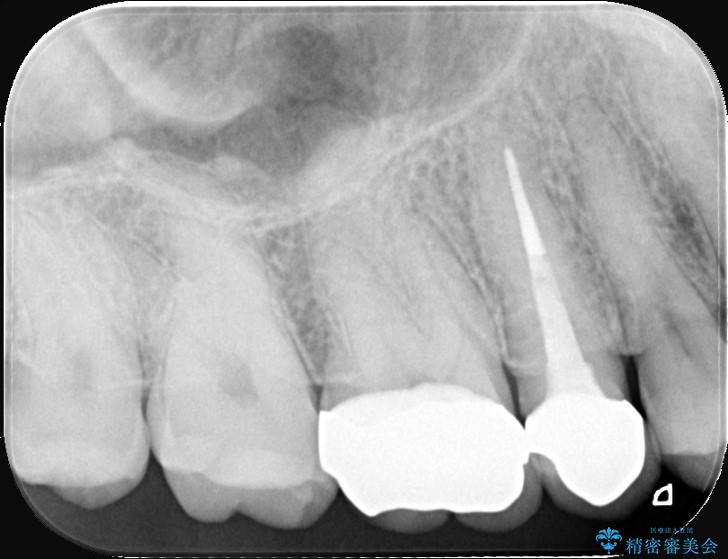

検査の結果、銀歯の下の歯質が薄くなっており、このままだと割れてしまう(破折)リスクが高い状態でした。

歯を長く守るため、セラミッククラウンでしっかりと補強し、強度と自然な見た目を両立させる治療をご提案しました。

まず、古い銀歯を丁寧に外し、内部に虫歯がないか確認しました。

その後、残りの歯を保護して強度を上げるため、適合性が高いオールセラミッククラウンの作成・装着を行いました。